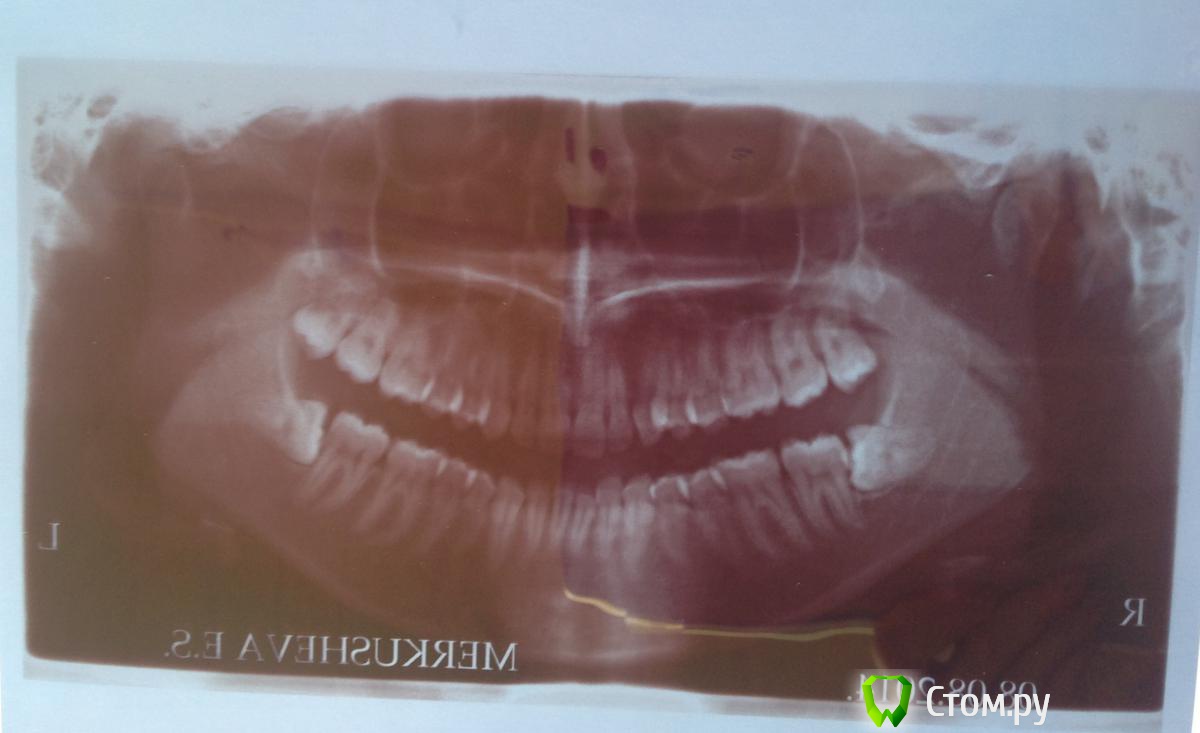

Елена11 Опубликовано 29 августа, 2014 Поделиться Опубликовано 29 августа, 2014 Здравствуйте, уважаемые стоматологи!Вопрос об удалении нижних ретинированных дистопированных зубов мудрости. 1) Врач городской поликлиники объяснил, что зубы расположены близко к нижнечелюстным нервам, в связи с чем есть опасность потери чувствительности или даже подвижности нижней челюсти, и дабы избежать подобного, направил меня в Московскую Областную Стоматологическую поликлинику. Сказал, что у них есть необходимая аппаратура, и что меня там положат в стационар. 2) в МОСП меня встретила молодая врач, которая сказала, что в стационар класть не будут, и по поводу возможности задеть нерв: «я не могу обещать, что не задену нерв, но потери подвижности не будет точно». При этом она сказала, что кроме имеющегося у меня снимка никаких обследований делать не нужно.Для меня непонятно, то ли первый врач излишне меня запугал, то ли вторая отнеслась несерьезно.Разумно ли в данной ситуации обойтись без госпитализации, есть ли необходимость проводить какие-то обследования кроме имеющегося снимка, и могут ли эти 2 операции быть проведены в обычной стоматологической поликлинике, просто у хирурга, которому я как врачу буду доверять, или стоит поискать какое-то специфическое мед. учреждение? Если да, посоветуйте, пожалуйста, подобные учреждения в Москве. Ссылка на комментарий

dr-krasnov Опубликовано 29 августа, 2014 Поделиться Опубликовано 29 августа, 2014 Не увидел ничего особенного. Сделайте КЛКТ для уточнения топографии и все будет хорошо, уверен. Ссылка на комментарий

red_butler Опубликовано 29 августа, 2014 Поделиться Опубликовано 29 августа, 2014 При квалифицированном подходе абсолютно рутинные удаления. Стационар не нужен, в идеале удаление под седацией. Ищите хирурга. Загляните во врачебный хирургический раздел, и поймете, что ваши зубы не такие уж и "страшные"По поводу потери чувствительности, всегда возможные осложнения оговариваются до а не после лечения. Вероятность подобного в вашем случае - низкая 3 Ссылка на комментарий